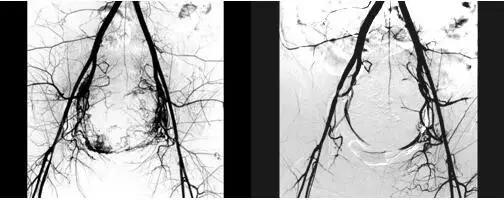

动静脉畸形所致AUB的病因有先天性或获得性(子宫创伤、剖宫产术后等),多表现为突然出现的大量子宫出血。

诊断首选经阴道多普勒超声检查,子宫血管造影检查可确诊,其他辅助诊断方法有盆腔CT及MRI检查。

治疗上,有生育要求的患者,出血量不多时可采用口服避孕药或期待疗法;对于出血严重的患者,首先维持生命体征平稳,尽早采用选择性子宫动脉血管栓塞术,无生育要求者,可采用子宫切除术。

(图:子宫动脉造影栓塞术:左图术前,右图术后)